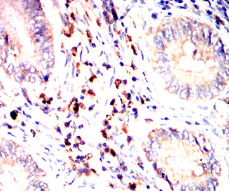

IHC    1/200 - 1/1000